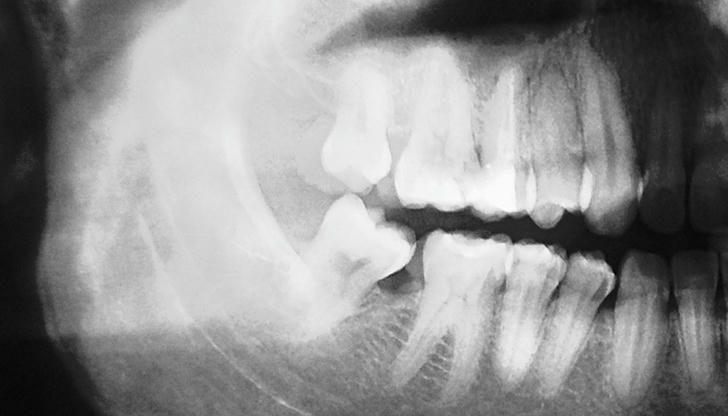

Correct Incorrect Wisdom teeth typically emerge in the late teens or early twenties, often causing impaction or crowding due to limited jaw space.